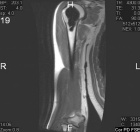

28 y/o male eight years s/p curettage and cementation for a right proximal humerus lesion found to be an aggressive enchondroma; presents with increasing R shoulder pain, worse with activity and direct pressure

PE: Healed surgical scar R shoulder, no TTP, mild edema, no LAN; FAROM, neurovascularly intact, 5/5; pain reproduced with shoulder extension and pulling